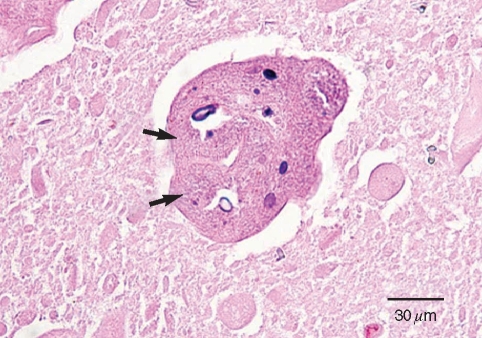

An Imported Case of Echinococcosis of the Liver in a Korean Who Traveled to Western and Central Europe

The Korean Journal of Parasitology 2010;48(2):161-165.